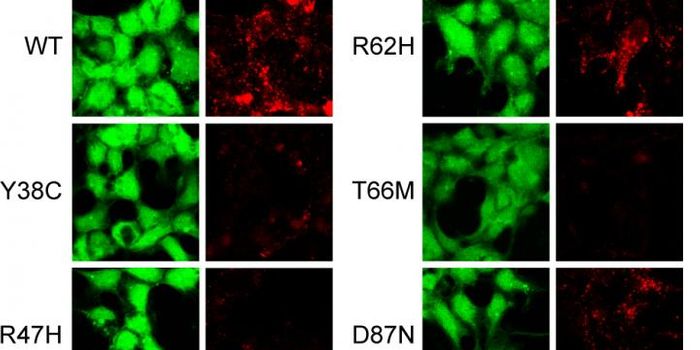

MAY 11, 2016ImmunologyNew Findings Could Be a Step Toward Preventing Autoimmune Disease A new study led by scientists at The Scripps Research ...